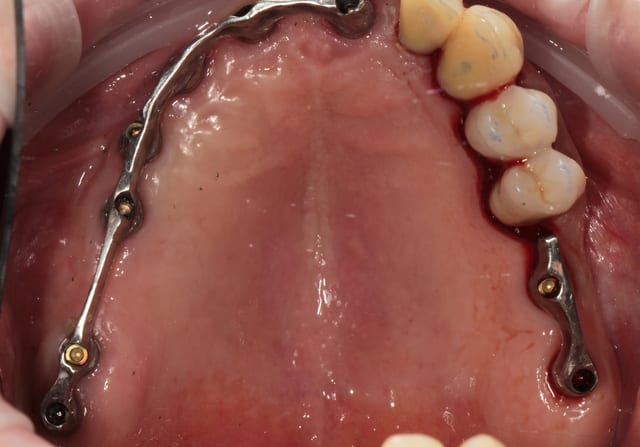

barre transvissée, chapes télescope, fausse gencive céramique au contact gingival et fausse gencive résine au collet des dents.

j'ai presque tout réalisé, de l'étude du cas, à la pose avec expansion et, ou implant court et sinus lift en passant par le choix des dents et la fabrication de la prothèse afin de pouvoir donner un avis de l'intérieur pour que les prothésistes puissent le faire la prochaine fois si ça fonctionne bien.

seule la cuisson opaque et gencive céramique est l'œuvre de Brigitte.

La partie Hot pour le béotien que je suis à été le fraisage de la cire et ensuite des barres.

Les mauvaises surprises et les difficultées ont concernées la liaison fausse gencive céram/résine et la tenue des dents résine.

sur les photos il s'agit bien de la liaison céram/résine c'est simple, pour le moment la limite ne se voit pas.